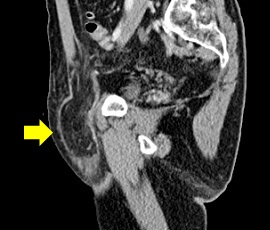

検診にて左下腹部の腫脹を指摘され受診。精査の結果、鼡径ヘルニア嵌頓(かんとん)と診断。手術(腹腔鏡下ヘルニア手術(TAPP法))を施行した。

CT画像